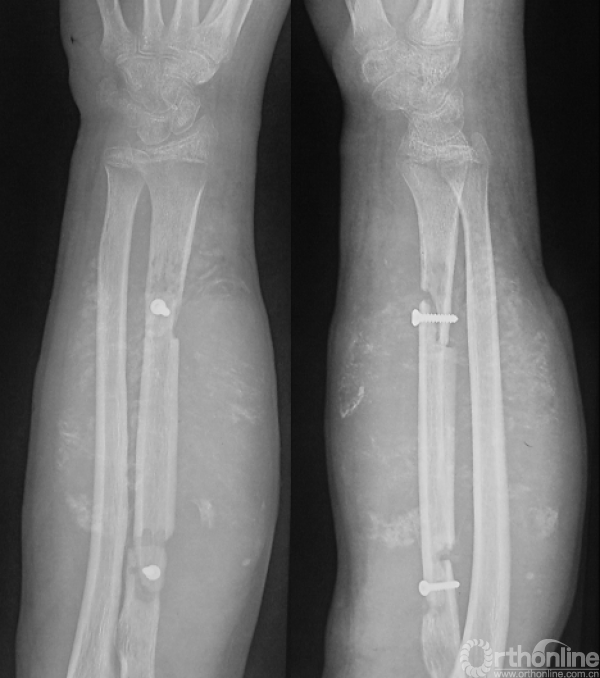

图14-4 术后3月X线平片正侧位

图14-5 术后3月平扫CT

体格检查(入院时)

右前臂明显肿胀,可见多处手术疤痕,可触及肿物,质硬韧,边界不清,无活动度,可及压痛,局部皮色暗红,皮温稍高,未见破溃及静脉曲张。右肘关节及腕关节活动不受限。

影像学检查(入院时)

图14-7 入院时X线平片正侧位(第一次术后3个月)

图14-8 入院时CT轴位骨窗、软组织窗、软组织增强窗(第一次术后3个月)

图14-9 入院时肺CT(第一次术后3个月),可见右肺结节影